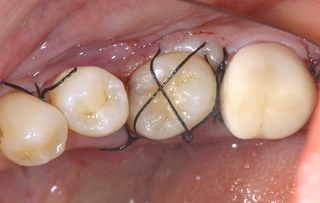

CASE

左下の一番奥歯が虫歯で抜歯となった30歳 女性

BEFORE

虫歯が大きく歯を残すことができずに抜歯となってしまいました。

レントゲンです。 向かって左端上の親知らずを、右下の奥に移植します。

AFTER

左の写真が親知らずを移植した直後のものです。 その後、根の治療をしクラウンを被せた状態の写真が右です。

移植後のレントゲンです。 BEFOREのレントゲンで空白だった部分におさまているのがわかると思います。